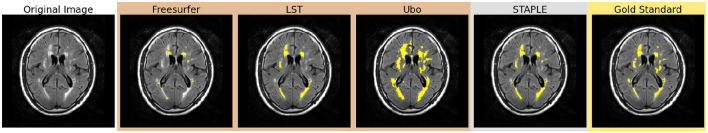

Methods: To address this challenge, we implemented a multi-stage semi-supervised learning (M3SL) approach that first uses un-annotated data segmented by traditional processing methods ("bronze" and "silver" quality data) and then uses a smaller number of "gold"-standard annotations for model refinement. The M3SL approach enabled fine-tuning of the model weights with the gold-standard annotations. This approach was integrated into the training of a U-Net model for WMH segmentation. We used data from three scanner vendors (over more than five scanners) and from both cognitively normal (CN) adult and patients cohorts [with mild cognitive impairment and Alzheimer's disease (AD)].

Results: An analysis of WMH segmentation performance across both scanner and clinical stage (CN, MCI, AD) factors was conducted. We compared our results to both conventional and transfer-learning deep learning methods and observed better generalization with M3SL across different datasets. We evaluated several metrics (F-measure, IoU, and Hausdorff distance) and found significant improvements with our method compared to conventional (p < 0.001) and transfer-learning (p < 0.001).